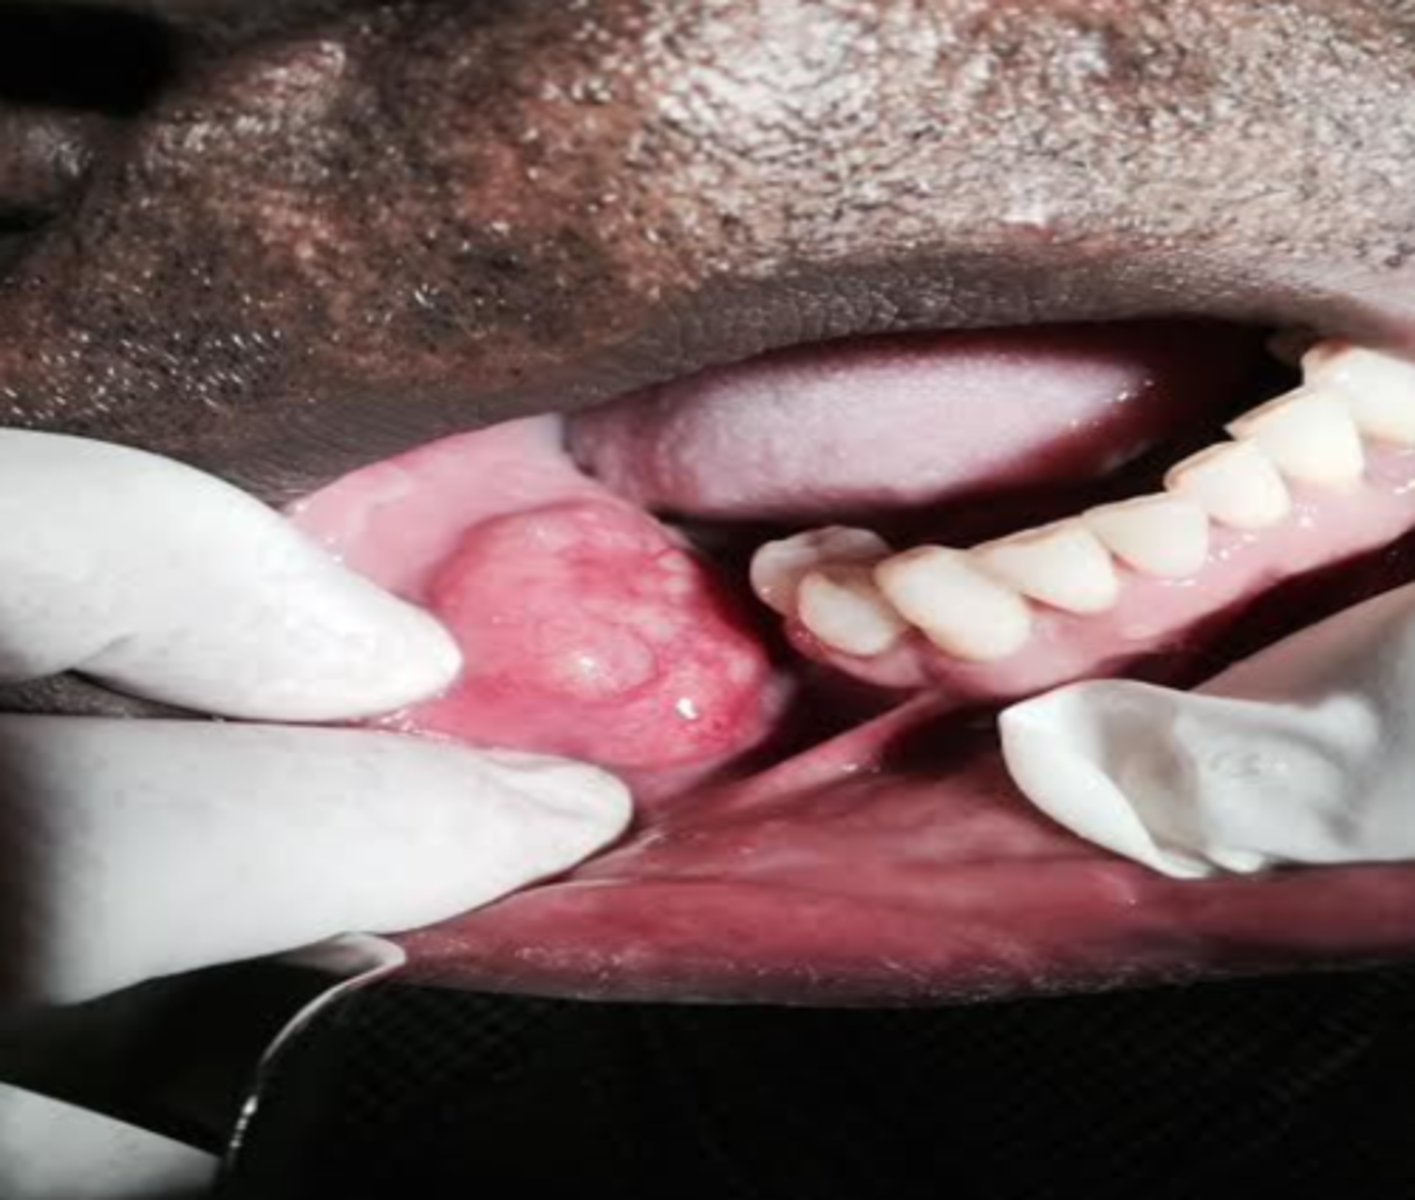

Mucoepidermoid Carcinoma

what is the Most common malignant salivary gland tumor?

Malignant Salivary Gland Tumors:

-Most common malignant salivary gland tumor

-Most common malignant salivary gland tumor in children

Parotid gland (major salivary

gland) (45%), Hard palate (minor) (21%)

Most common sites for Mucoepidermoid Carcinoma

mucocele

What can Mucoepidermoid Carcinoma mimic?

-Epidermoid cells

-Mucous cells

-Ductal structures

-Cystic spaces

-CRCT1-MAMl2 translocation ⇒ t(11;19)

Mucicarmine Stain